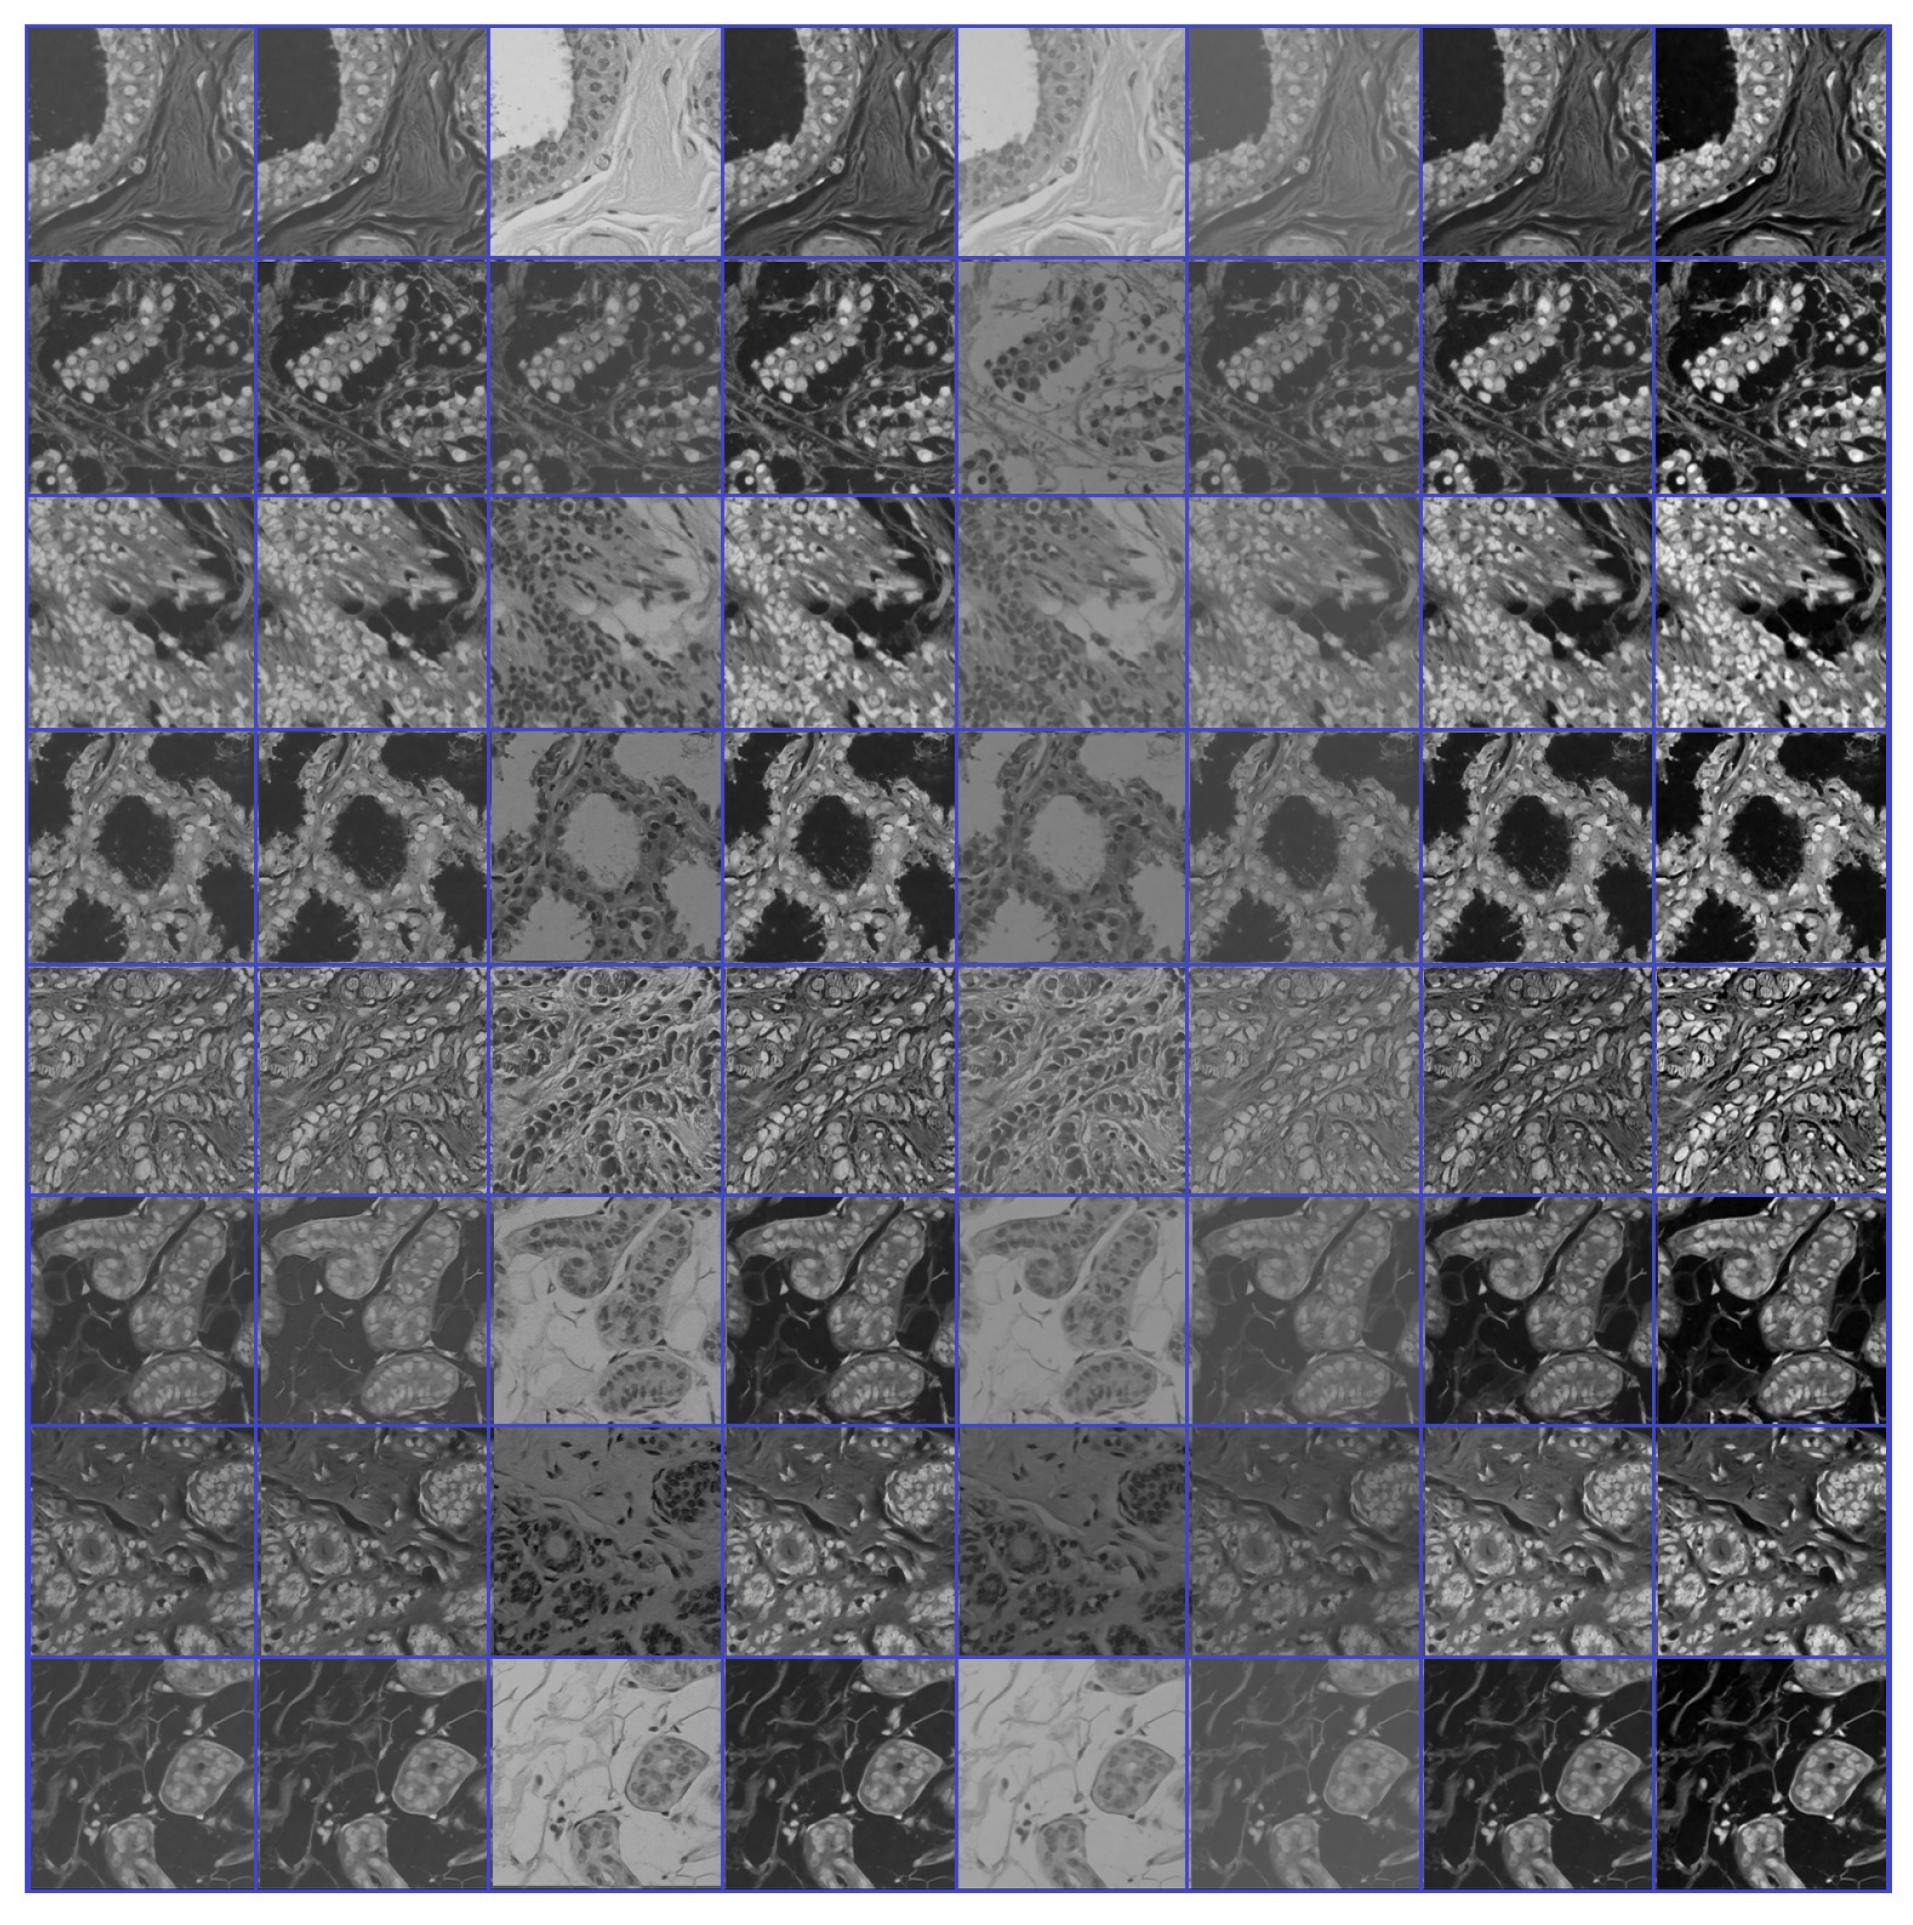

- Source domain dataset of breast cancer: we collected the histopathology images of breasts from various sources. The first source is the BreakHis dataset [52]. This dataset is composed of 9109 microscopic images of breast tumor tissue with a size of 700 × 460 pixels. Each image was divided into two images of 350 × 230 and then resized to 512 × 512. The second source is the histopathological microscopy image dataset of IDC [53]. It consists of 922 images with sizes of 2100 × 1574 and 1276 × 956 pixels. The third source is the breast cancer dataset, which is composed of 537 H&E-stained histopathological images with a size of 2200 × 2200 pixels [54]. The fourth source is the BreCaHAD dataset [55]. This dataset consists of 162 breast cancer histopathology images with a size of 1360 × 1024 pixels. The fifth source is the SPIE-AAPM-NCI BreastPathQ dataset [56], which is composed of 2579 patches of histopathology images of the breast. These patches were extracted from 96 images with a size of 512 × 512. The sixth source is the image dataset from the bioimaging 2015 breast histology classification challenge [57]. There are 249 images with a size of 2040 × 1536 pixels. All the images of sources two to six were divided into 12 nonoverlapping patches of 512 × 512 sizes. The total was 50,314 breast histology patches. All collected patches were duplicated to more than 200,000 images by using data augmentation techniques. It is worth mentioning that we cropped the images to 512 × 512 to fit the input size of the model. This guarantees that the proposed model detects the features that define the nucleus-localized organization and the overall tissue architecture required to distinguish between the classes. Conversely, taking a small size could result in a loss of information associated with the same assigned class of the entire image. Figure 4 shows some samples of the dataset.

- Phase #2: Training our model on source domain dataset of skin cancer. We then fine-tune the model for the target dataset of the skin cancer classification task (see Figure 2). Figure 8 shows the learned filters from the first convolutional layer. The learned filters from the first convolutional layer indicate that our model learned excellent features from the beginning.